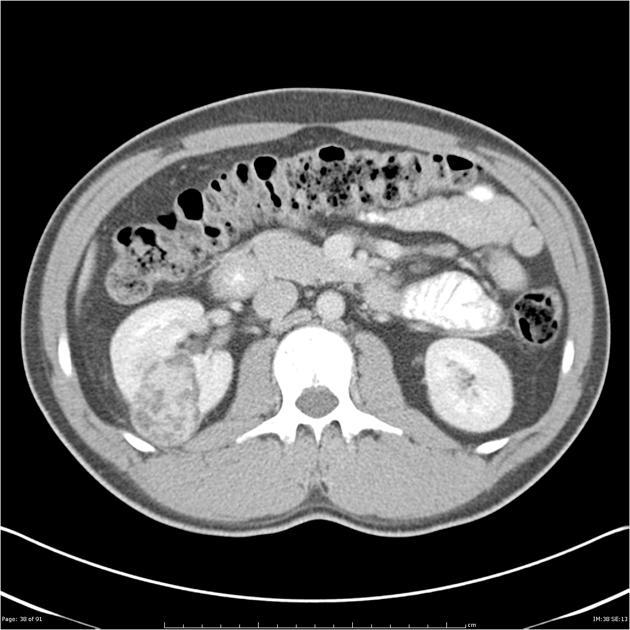

medullary nephrocalcinosis

bosniak classifcation?

2F

bosniak classification?

bosniak I

no septa, very simple